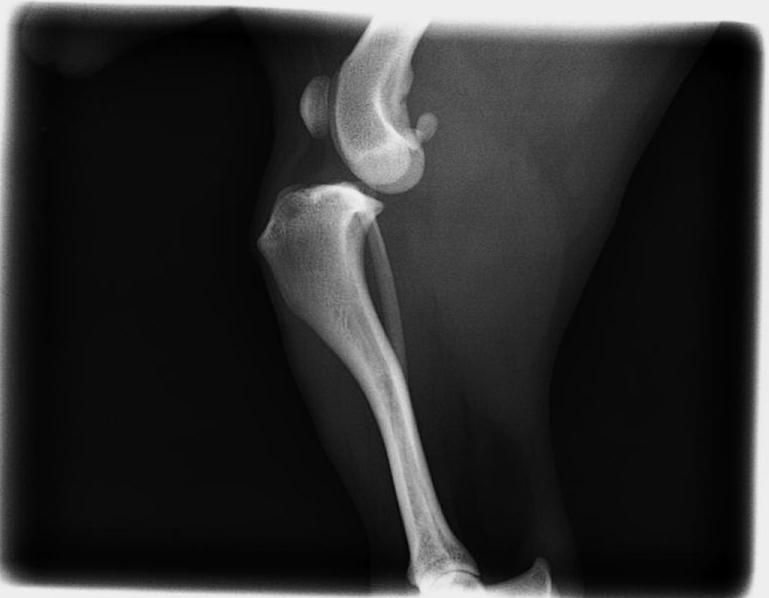

Enfermedad de Legg-Perthes

Consiste en la necrosis avascular de la cabeza del fémur, produciendo mucho dolor en la articulación, cojeras y pérdida de masa muscular. Suele aparecer en animales toy a la edad de 6-7 meses. Se diagnostica por medio de radiografías, y es muy importante operarles lo antes posible, para que su recuperación sea más ràpida.

La operación consiste en hacer una artroplastia por escisión de cabeza y cuello del fémur, y los resultados son muy buenos si se hace una correcta rehabilitación postquirúgica.